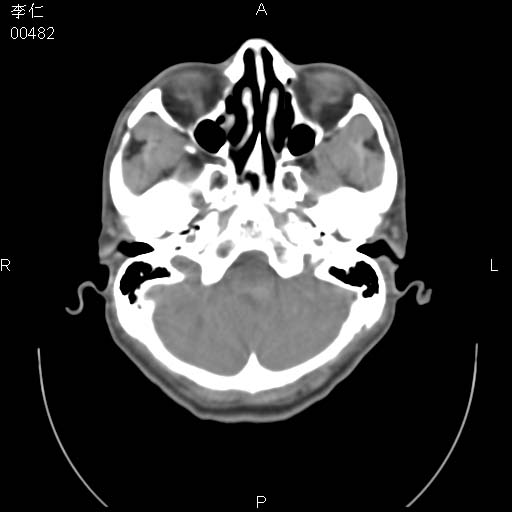

患者男,45岁。于二月前发现左眼稍肿,去看眼科,查肾功(—),来查ct,我看到的是左侧上眼睑内低密度影,ct值是-600到-700hu。

是一个副鼻窦的正常变异,脂肪瘤的密度不可能这么低,-600到-700.

只是空气而已,属正常ct表现。

正常表现,眼睑与结膜zhi间的空气

正常,为结膜囊内气体。

左侧眼球壁光滑,未见异常密度灶,眶内结构清晰,眼内肌、视神经均正常。所见低密度灶,本人考虑:1、五官科翻上睑造成;2、炎症(产气细菌感染)。